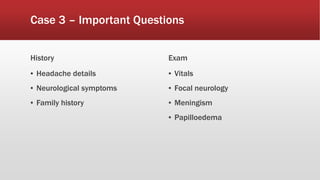

This document discusses various cases of collapse and syncope. It defines collapse as transient loss of consciousness with loss of postural tone and full recovery. Syncope is defined as loss of postural tone with or without loss of consciousness and full recovery. It then discusses the multiple potential causes of collapse and syncope including toxicological, cardiac conduction abnormalities, structural cardiac issues, autonomic dysfunction and more. It then goes through 9 case examples, discussing important questions to ask, potential tests and interventions for each case.